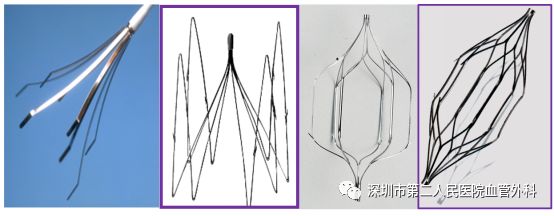

微创腔内介入技术对血栓当然大有可为。目前主要包括导管接触性溶栓方法(英文简称CDT)和经皮机械血栓清除术(英文简称PMT)这两种方法,有的时候两种方法经常联合使用。

CDT是将带有很多侧孔的溶栓导管,通过静脉穿刺的方法插入血栓中,将溶栓药物通过侧孔持续推注到血栓中,可获得很好的溶栓效果(图10-12)。这种方法对静脉壁损伤轻微,而且能较好地保护静脉瓣的功能。

图10 带有侧孔的溶栓导管

PMT是经皮机械血栓清除术,目前国内临床使用的主要是AngioJet Ultra 血栓清除系统,其原理是运用了流变学伯努利原理,能够有效清除血栓,迅速减轻血栓负荷,使症状快速获得缓解;快速开通血管,恢复血流,改善远端血供;减少平均住院时间,节省整体治疗费用。(图13-14)

图13 血栓被喷射水流击碎、被吸进导管并排出体外

图14 PMT手术治疗前后即刻效果

肺栓塞是一种非常危险、猝死率很高的疾病,其预防的重要性不言而喻。卧床静养、抗凝治疗是最基本的预防,而最有效的预防措施是在血栓远端的下腔静脉值入滤器。滤器有多重形状(图15),它允许血液自由通过,而如果脱落的血栓流经此处,则被滤器拦住,不会继续前行发生肺栓塞(图16)。

图15 各种不同形状的滤器

图16 滤器植入下腔静脉后血液仍能通过